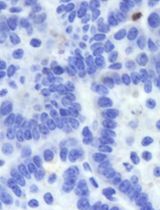

- On Day 11, image the plate to quantify residual viable tumor by analyzing mCherry fluorescence (see Figure 1B).

Figure 1. Photodynamic therapy of 3D ovarian cancer nodules. A. A schematic representation of how PDT is performed on the 3D ovarian cancer nodule grown on beds of Matrigel. Scale bar: 500 µm. B. Representative fluorescence images of 3D tumor nodules following 10 J/cm2 PDT treatment are shown along with ‘no treatment’ control. Images were taken 4 days after PDT treatment. Scale bars: 500 µm. C. Quantification of mCherry-expressing tumor area was performed using a high-content imaging system and presented as ‘fraction tumor area’ (residual live tumor area) in the graph after normalizing to ‘no treatment’ control. Images were adapted and reproduced from a published article (Rizvi et al., 2019) with written permission from the publisher.